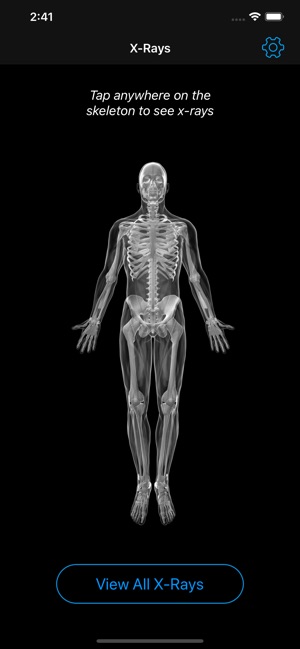

Your pocket sized x-ray reference tool. Gain confidence in x-ray interpretation with this complete atlas of radiographic anatomy, large collection of normal reference studies, and cases that include diagnoses, management and follow-up studies.

• A complete radiographic atlas of human anatomy